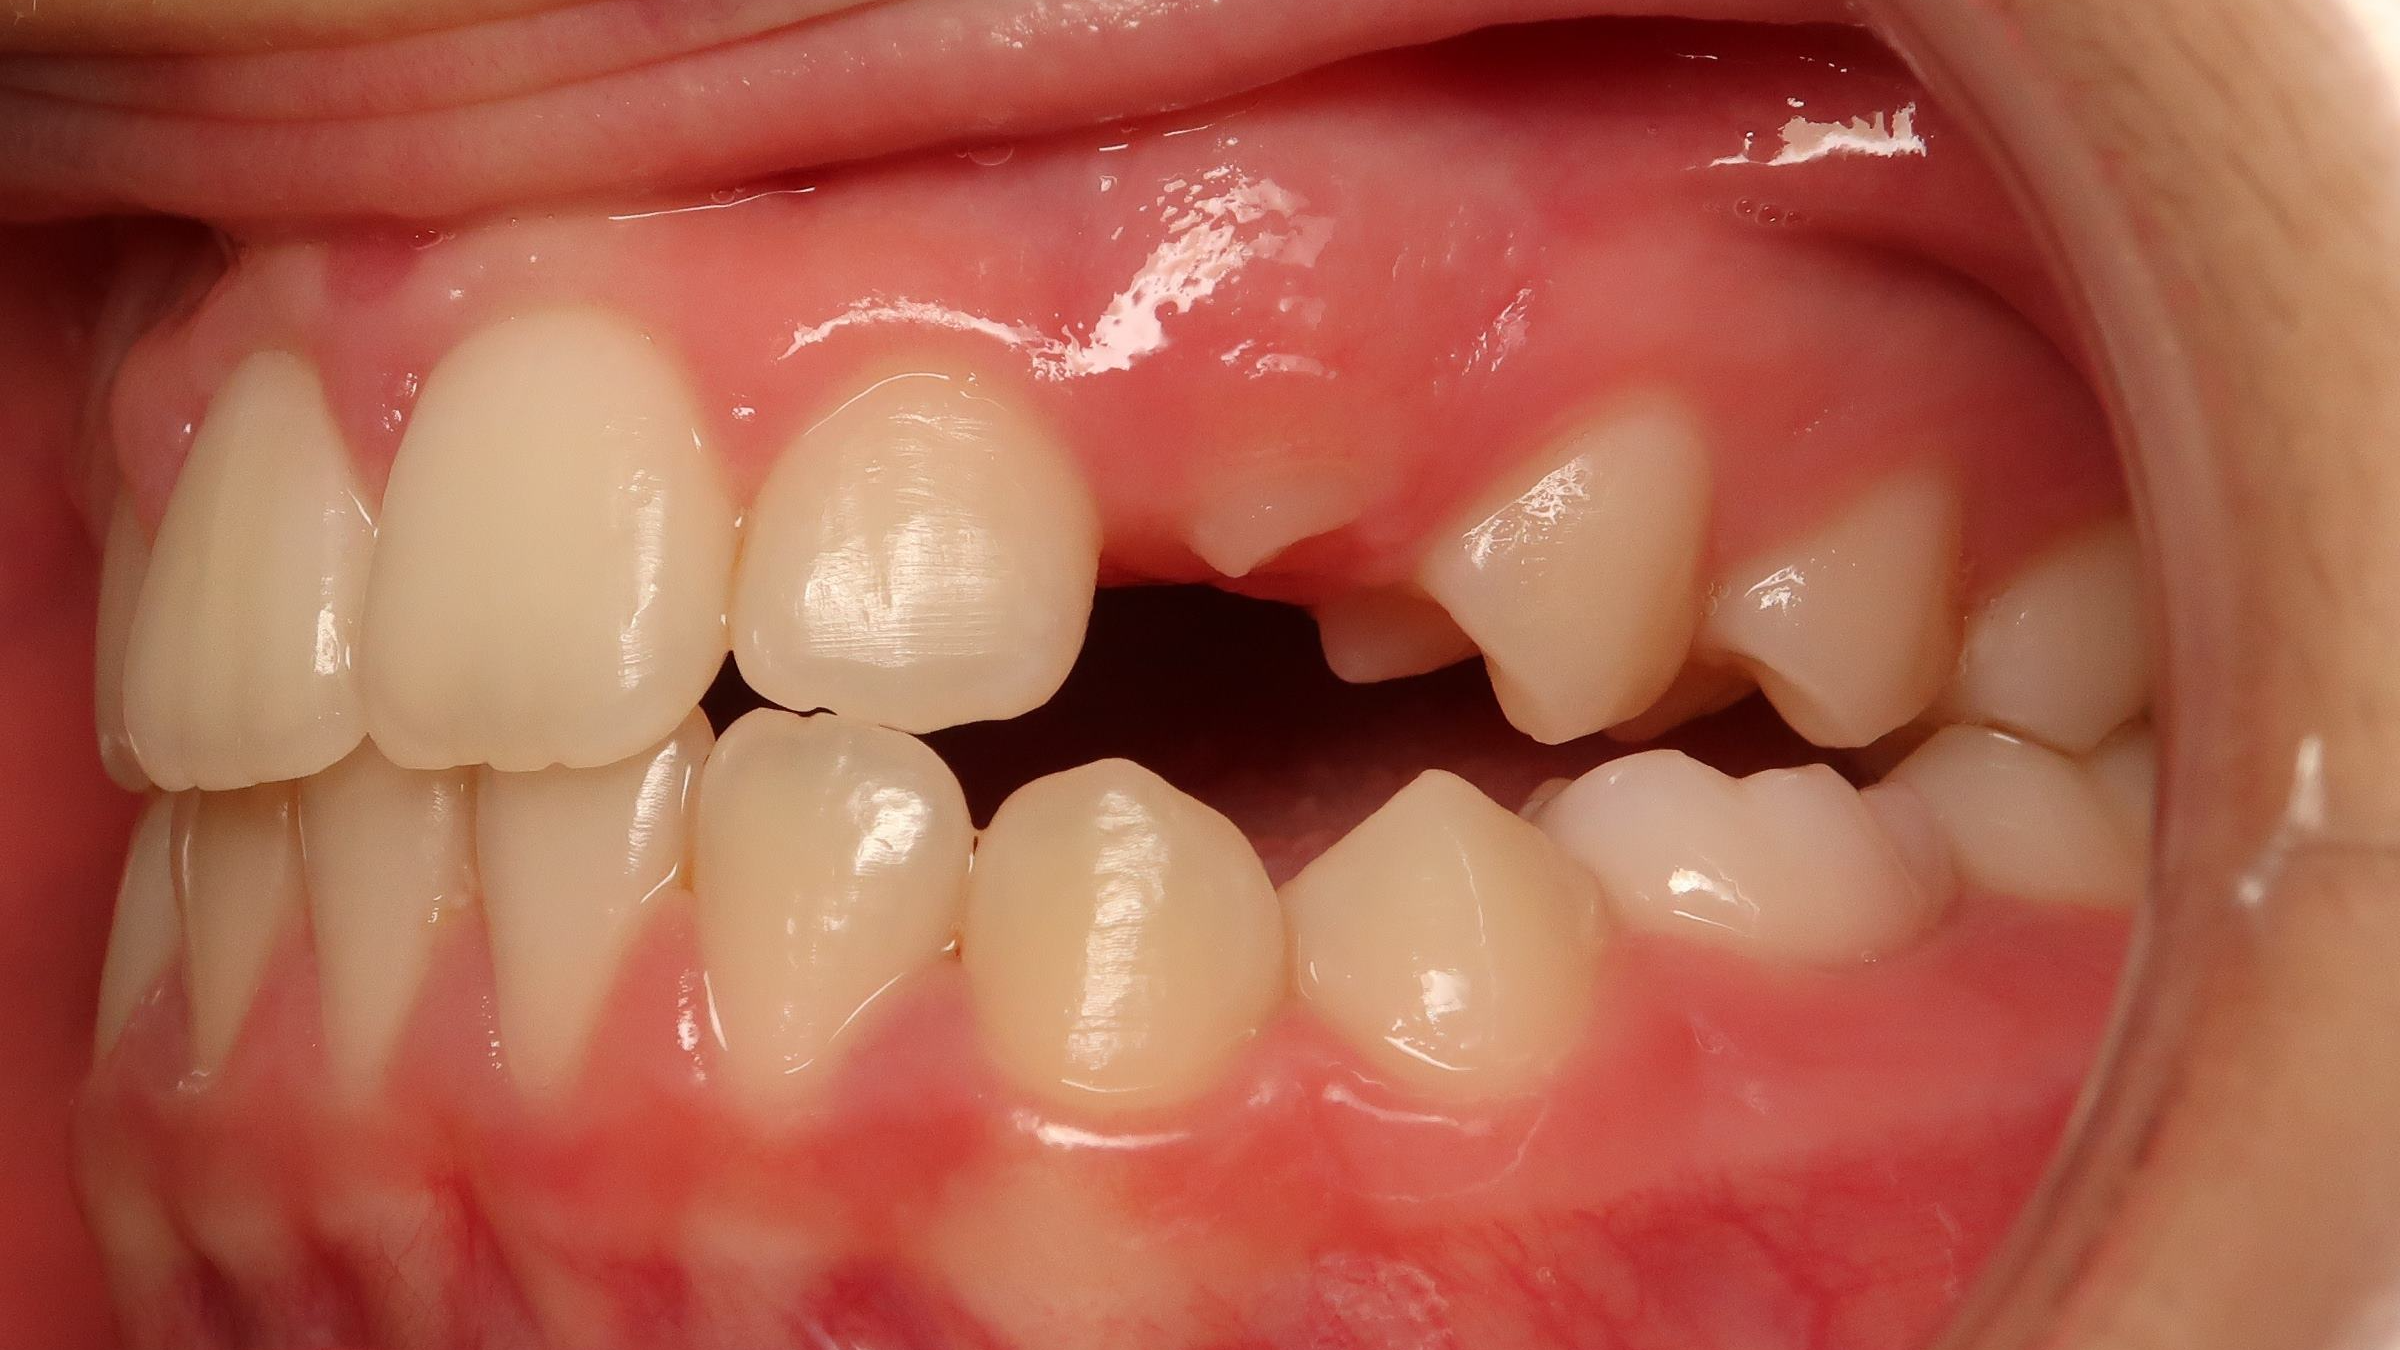

25. bout à bout anterieur 6 ans

dents du haut bout à bout par rapport à celle du bas